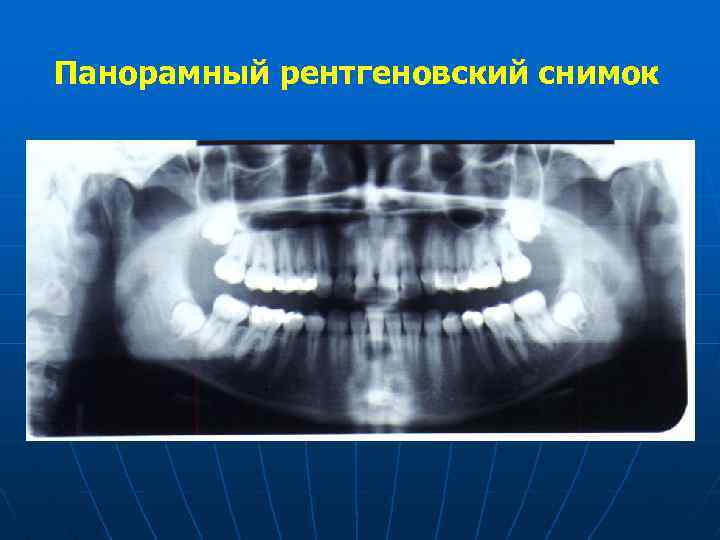

Внутриротовая рентгенография Телерентгенография Рентгенологическое обследование Панорамная рентгенография Ортопантомография

Панорамный рентгеновский снимок